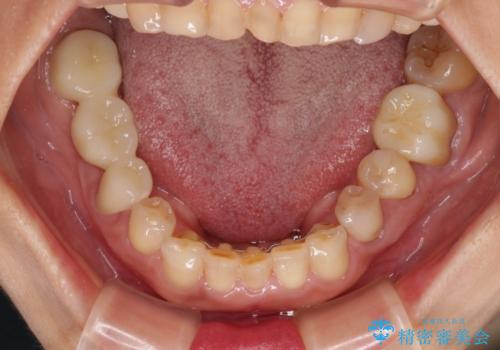

並行して左下にはインプラントを埋入し、矯正治療を終えると同時に補綴治療を行うこととしました。

過蓋咬合(下顎前歯が隠れてしまうほどの深い咬み合わせ)のため、スムーズに歯が動かず矯正治療に時間がかかりましたが、無事に仕上げることができました。